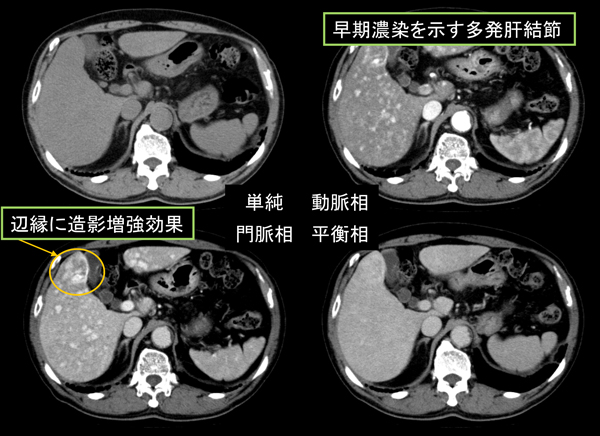

肝細胞癌のCT,MRI画像診断 HCC:hepatocellular carcinoma。